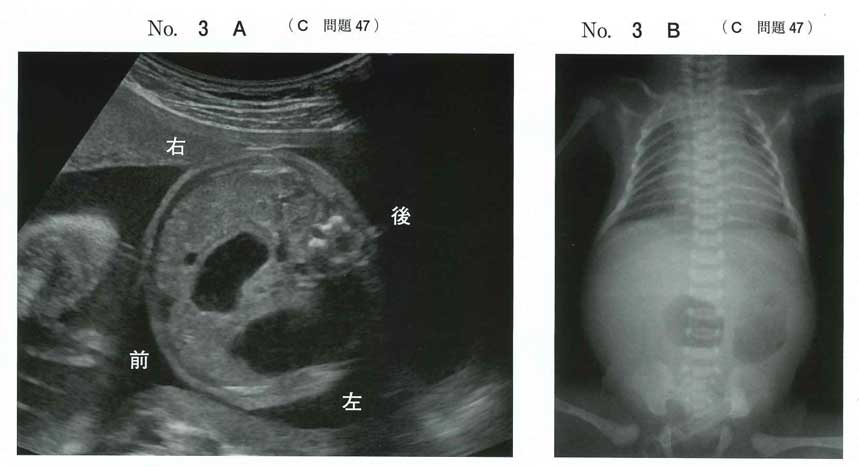

検査からは十二指腸閉鎖症とそれに伴うdouble-bubbleサインが読み取れます。

眼裂斜上と平坦な鼻根部と合わせ、21トリソミーが疑われます。

染色体核型の記載としては、47, XX, +21となります。